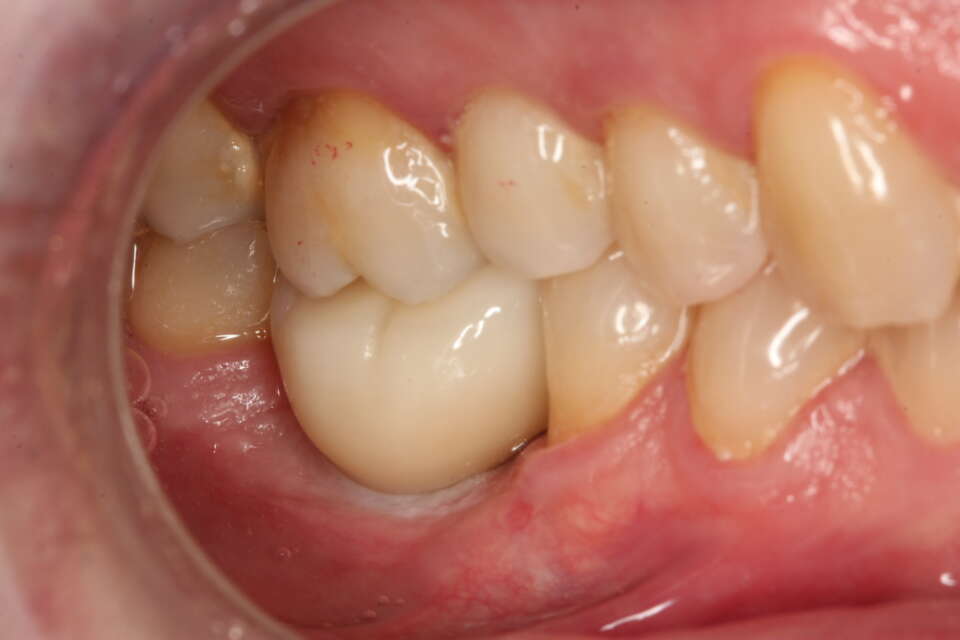

IMG 8049

Molar restored on the right side

IMG 8050

Molar restored on the left side

IMG 8052

Just look at the size of the restored molars. The impact on eating cannot be underestimated

The treatment was planned, designed and completed by Dr Nissit Patel using TRI Matrix tissue level dental implants.